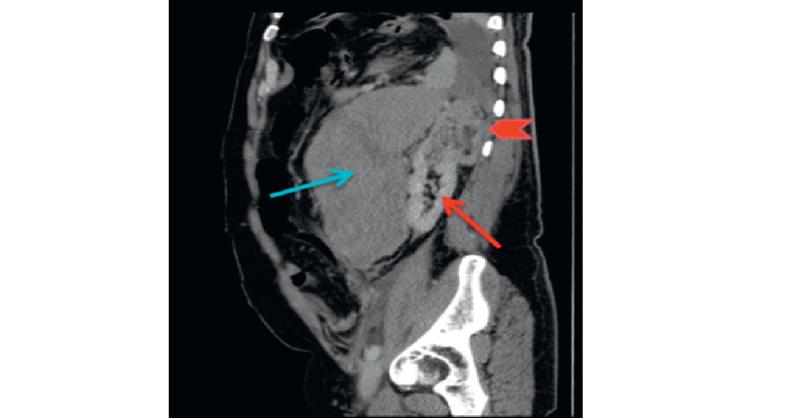

Spontaneous Retroperitoneal Bleeding in 58-Year-Old Man

A 58-year-old man presented to the emergency department complaining of left-side abdominal pain for four days. The pain began suddenly and moved to the left groin and testes. However, it was only associated with constipation through passing flatus. There was no history of vomiting, sweating, palpitation, or hematuria. There was no past medical hist